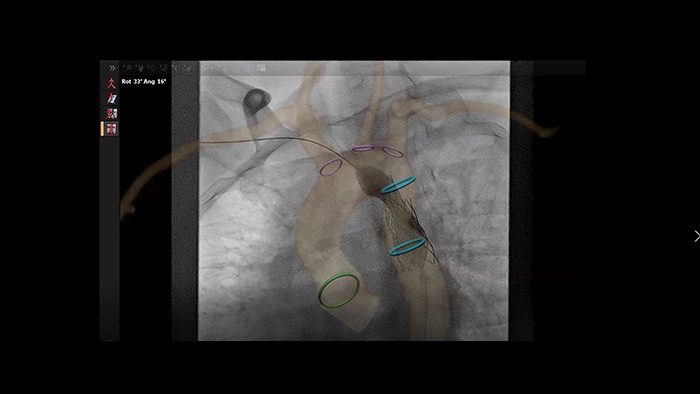

Guía de colocación de stent en coartación aórtica con VesselNavigator